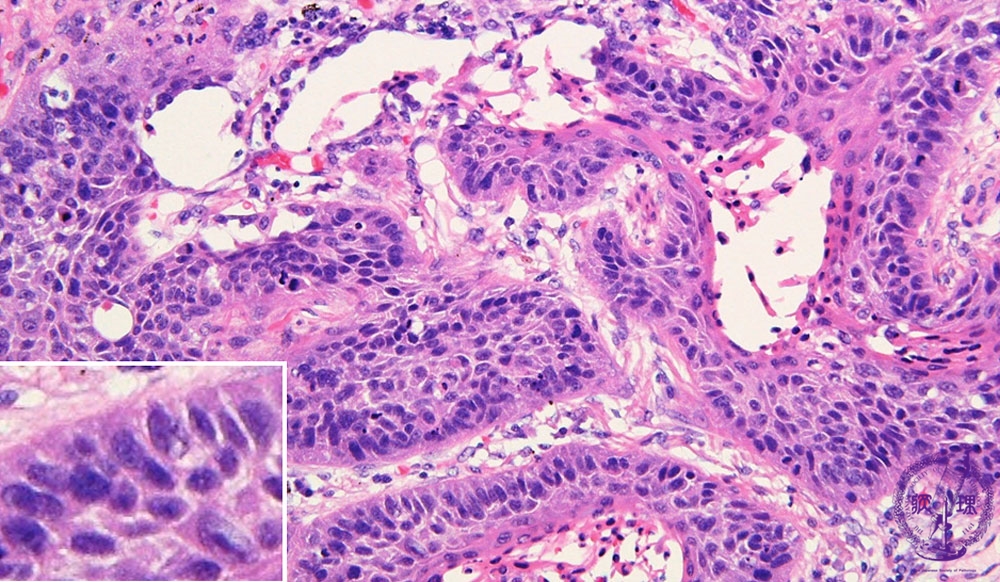

- ★(17)Non-small cell lung carcinoma(squamous cell carcinoma)

Microscopic view (HE stain, high power view): Squamous cell carcinoma of lung. Tumor cells proliferate in sheets while maintaining intercellular bridges (left lower inset). The cytoplasm is eosinophilic and elongated, features indicative of keratinization (arrow).